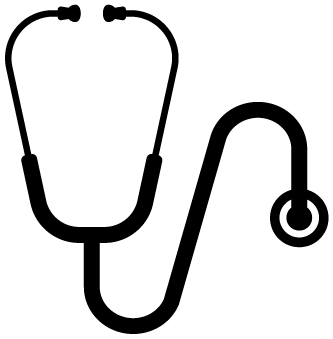

WHAT IS BLEPHARITIS

Blepharitis is an infection of the eyelash glands and eyelids. The infections are usually bacterial or from a mite (Demodex). Because this infection affects the tear glands, it causes a disruption of the important function of the tears and results in a Dry eye syndrome.

HOW IS BLEPHARITIS DIAGNOSED

Blepharitis infection is almost always associated with dry eye syndrome. This complex relationship requires meticulous diagnostic tests & management by Dr. Djan at the Advanced Dry Eye Clinic. The reasons for this are simple: No two people with blepharitis/dry eye syndrome have the same degree or cause of pathology. Tests are required to diagnose your specific degree of blepharitis so that a custom solution can be designed for you.

These diagnostic eye tests that Dr. Djan performs at the advanced Dry Eye Clinic are all non-invasive and include :

HOW IS BLEPHARITIS TREATED

A customised dry eye syndrome treatment is designed once your comprehensive assessment is complete. Depending on your classification, there a various options available to tackle DES: